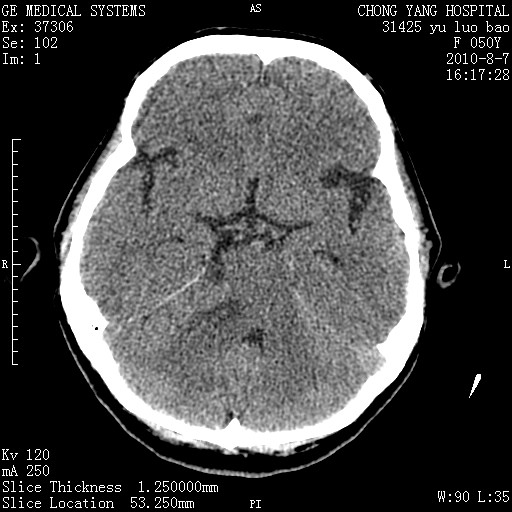

标题: CT28285:听力下降一年,头昏。 [打印本页]

标题: CT28285:听力下降一年,头昏。

右侧桥小脑角区占位--听神经瘤,建议增强或mri检查。

右侧桥小脑角去等密度占位,右侧内听道扩大、骨质吸收,考虑:右侧听神经瘤,建议增强检查。

右侧内听道扩大、骨质吸收,中脑受压左移,考虑:右侧听神经瘤,建议增强检查。支持!

骨窗示右侧内听道扩大,考虑右侧听神经瘤。

右侧桥小脑角区等密度占位,内耳道扩大,听神经瘤